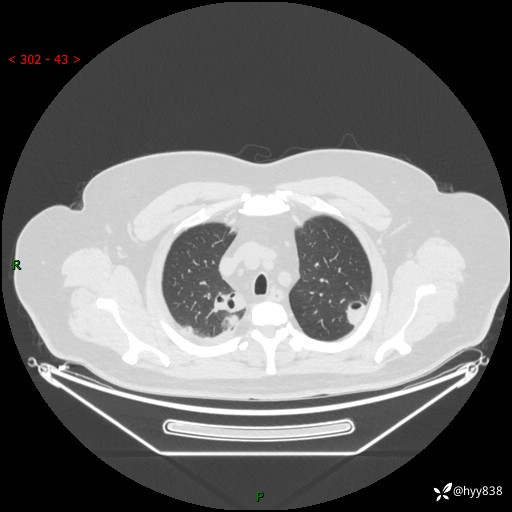

病例信息

性别:男

年龄:48岁

简要病史:发热来诊(门诊病人)

胸部CT平扫